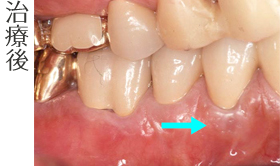

根面被覆術

審美歯周外科治療(根面被覆術)で歯茎を再生してセラミック冠を作成しました。

- セラミックブリッジ(4本)

- 審美歯周形成外科